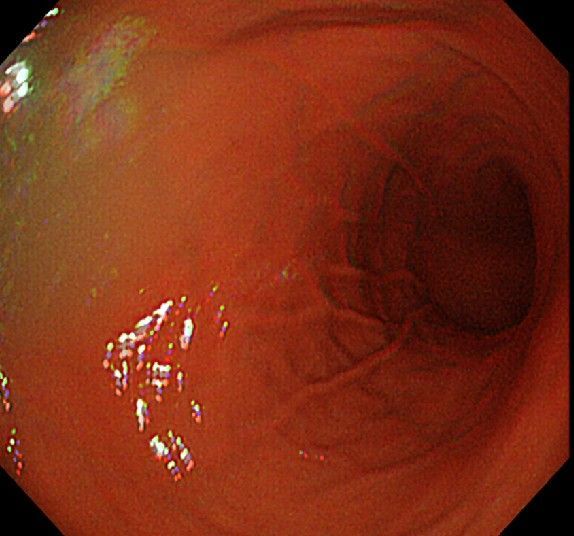

위 내시경을 찍었는데 위염 종류 사진을 알 수 있을까요? (사진 많습니다..)

한달 전 쯤에 소화불량과 속쓰림이 3개월 동안 약을 먹어도 낫지 않아 위 내시경을 찍었는데 위에 염증이 많이 있다는 이야기를 들었습니다...그런데 상태가 얼마나 안 좋은지 어떤 종류의 위염인지에 대해서는 물어봐도 안 알려주셔서 여기에라도 올려서 여쭈어봅니다... 제 상태가 얼마나 심각한 걸까요..

• 1번 째 사진

안녕하세요. 이욱현 의사입니다. 심각한 상황이 아닌 것으로 보이고 특별한 종류의 위염도 아닌 것으로 보입니다. 너무 걱정하지 않으셔도 되겠습니다.

사진상으로 보아서는 정상에 가까운 점막상태이거나 약간의 표재성 위염이 있는 정도로 보입니다.

홍반성 위염이 있으며 경증의 역류성 식도염이 있습니다

위내시경상으로는 특이소견이 없다고 보셔도 됩니다